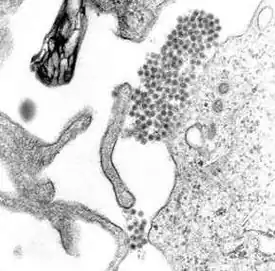

Flavivirus (лат.) — род арбовирусов из семейства Flaviviridae. Типовой вид — вирус жёлтой лихорадки. Преимущественно циркулируют между членистоногими (клещи, комары) и млекопитающими (приматы, летучие мыши, грызуны, скот). При укусе заражённого комара или клеща могут передаваться человеку, вызывая заболевания различной тяжести, варьирующей от бессимптомного протекания до угрожающих жизни геморрагических лихорадок и энцефалитов (лихорадка денге, лихорадка Западного Нила, лихорадка Зика, клещевой энцефалит, японский энцефалит, энцефалит Сент-Луис и др.).